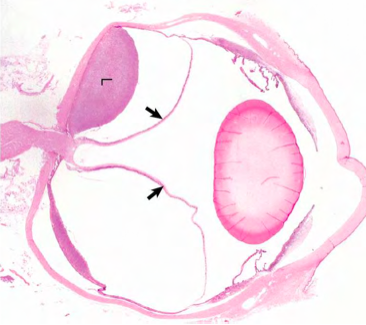

Retinal detachment due to effusion from the growth of metastatic lymphoma within the choroid and subretinal space

Retinal detachment (separation)

Consequence = retinal degeneration & atrophy

Separates between neural and pigmented layers